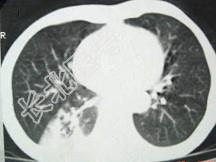

- 单项选择题男,40岁, 胸背疼痛一周,消瘦一月, CT检查如图,最可能的诊断为 ( )

A、右下肺结核

B、右下肺脓肿

C、右下肺炎

D、右下肺肺泡癌

E、右下肺炎性假瘤